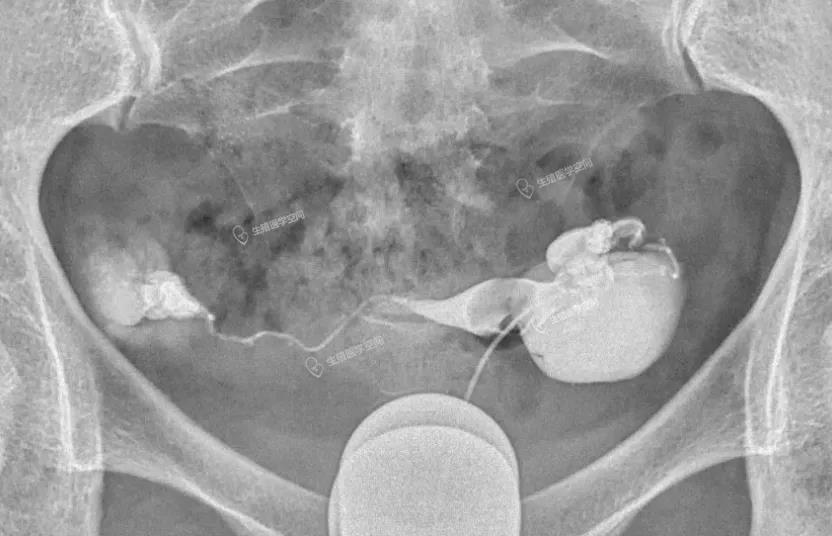

图5:双侧输卵管均栓塞多个弹簧圈

这两例都是所谓的致密栓塞,手术的医生自己也不自信,栓塞后手术结束前也不敢做一个造影看看效果。图4手术费花了1万9千多,右侧输卵管前几个弹簧圈掉进了宽大的积水管腔,没用一点栓塞作用。左侧输卵管栓塞是串联加并联。图5手术费是2万4千多,双侧输卵管栓塞的前几个弹簧圈都掉进了远段宽大的积水管腔,没用一点栓塞作用,起作用的就是最后一个弹簧圈。